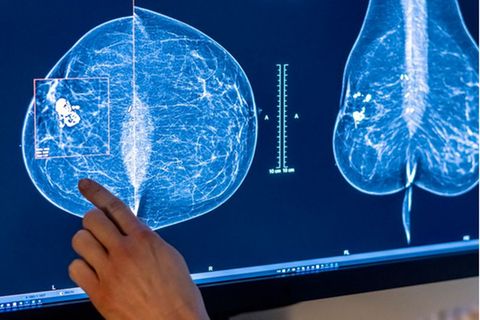

In Deutschland erkrankt etwa jede achte Frau an Brustkrebs. Welche Vorteile bietet das Brustkrebs-Screening für die Früherkennung? Und warum nutzen so wenige Patientinnen die Chance?

Gerade erst wurde die Ausweitung der Mammographie zur Früherkennung von Brustkrebs für Frauen bis 75 Jahre beschlossen. Ein neuer wissenschaftlicher Bericht empfiehlt nun auch die untere Altersgrenze weiter abzusenken